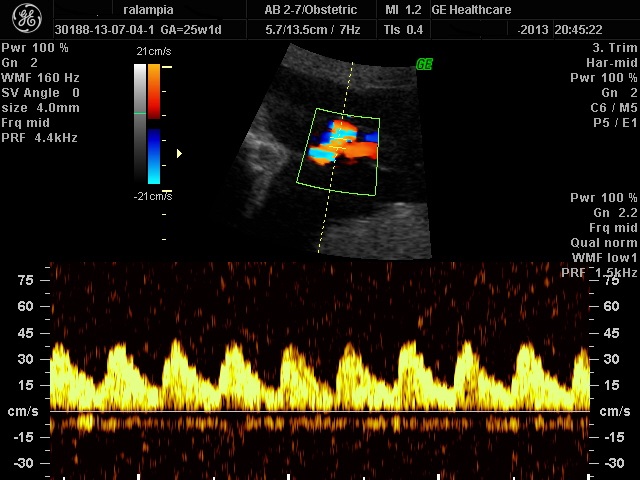

Τo υπερηχογράφημα ανάπτυξης - Doppler πραγματοποιείται μεταξύ 32 και 34 εβδομάδων κύησης. Ελέγχεται το βάρος του εμβρύου, η ομοιόμορφη σωματική αύξησή του, η κινητικότητα του εμβρύου, η ποσότητα του αμνιακού υγρού και η θέση του πλακούντα. Διενεργείται ένας αδρός επανέλεγχος της ανατομίας του εμβρύου και δια του έγχρωμου υπερηχογραφήματος Doppler η εκτίμηση της ροής του αίματος στην ομφαλική αρτηρία, στη μέση εγκεφαλική αρτηρία και όταν κρίνεται απαραίτητο και στο φλεβώδη πόρο. Τα αποτελέσματα αυτής της εξέτασης παρέχουν σημαντικές πληροφορίες για τη περαιτέρω πορεία της κύησης.